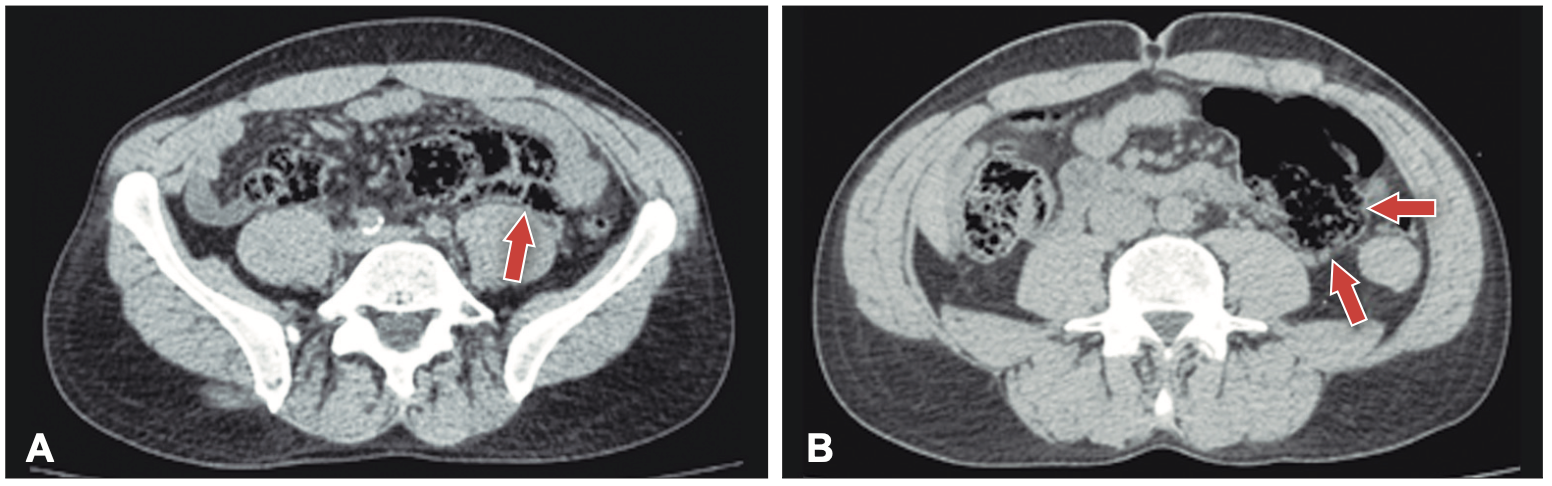

Posteriormente se realiza una tomografía computarizada de abdomen y pelvis sin contraste donde se observan asas intestinales dilatadas (Figura 1), ciego levemente distendido con abundante contenido propio, que cruza la línea media hacia el flanco izquierdo (Figuras 2 y 3), tracción e ingurgitación de los vasos mesentéricos (Figura 4).

Figura 2. A y B: Corte axial, donde se observa el ciego localizado hacia el lado

izquierdo